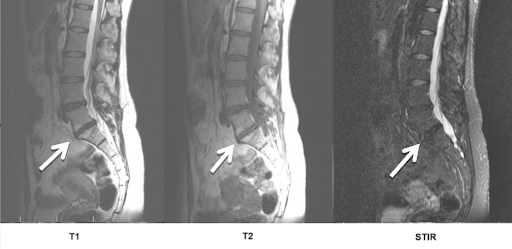

енение по типу modic 1